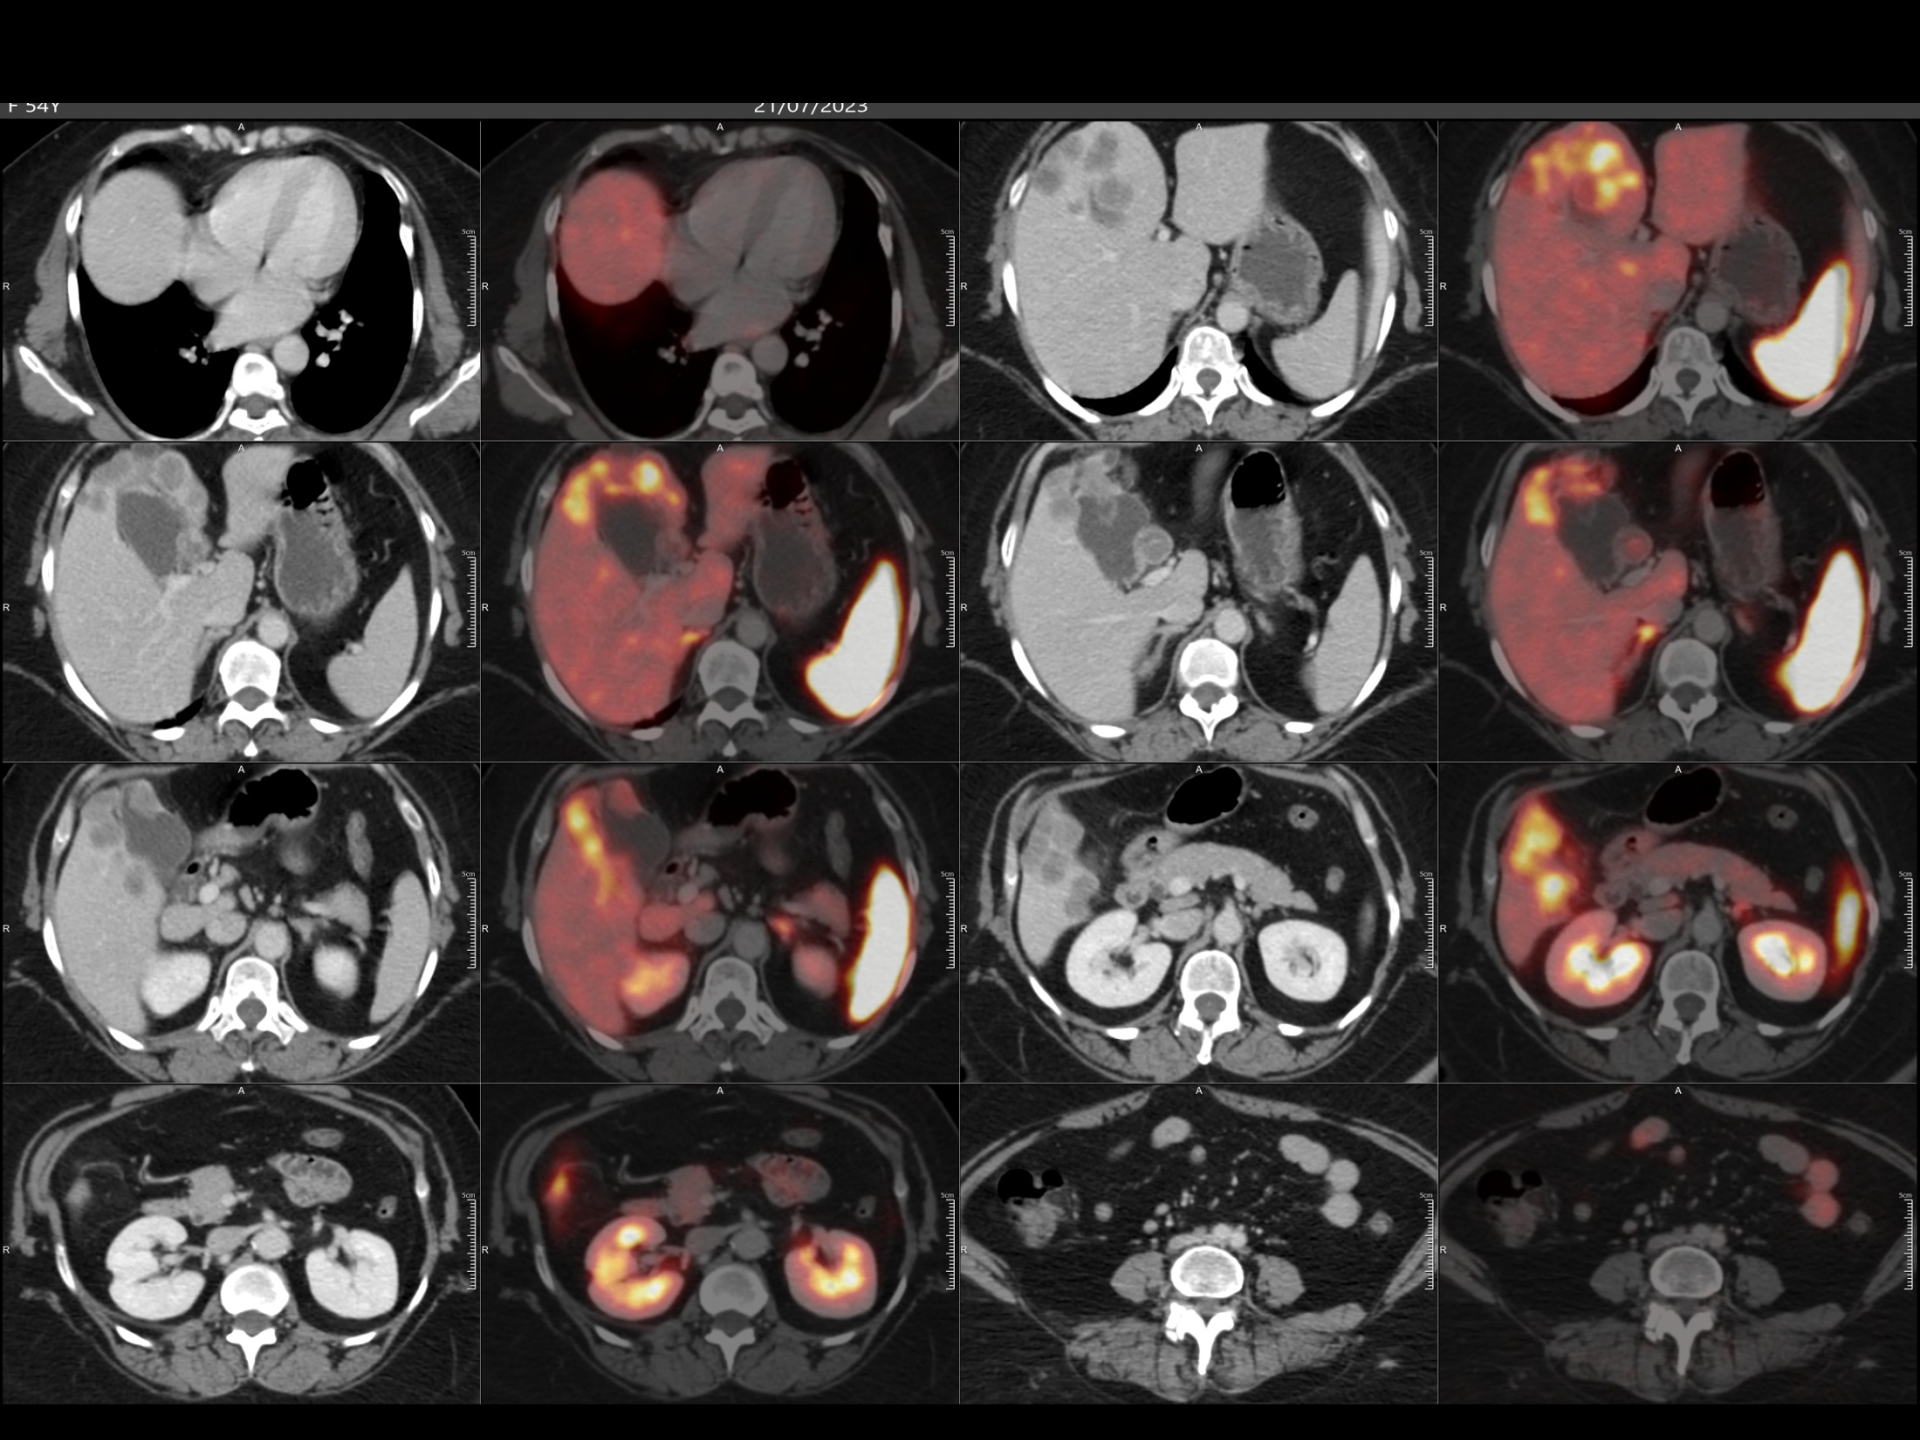

160 Slice Digital Pet-Ct

India’s first 160 slice High Resolution Digital PET-CT provides a revolutionary breakthrough in the combination of clarity, sensitivity, coverage and speed.

It is possible to get very good quality images even with a very low dose of FDG (Radiation) and less time.

Sensitivity of detecting very small lesions (upto size of 5 mm) is very high.

• PSMA for Prostate malignancy .

• Ga-DOTA to diagnose NET (Neuroendocrine tumors).